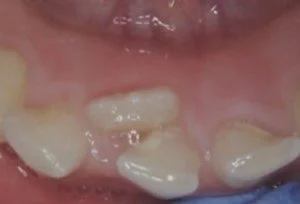

“Shark Teeth” or “Double Row of Teeth”

Special Note for Upper Front Teeth

If an upper front adult tooth is growing behind a baby tooth, it’s best to have it evaluated sooner.

Early removal of the baby tooth may be recommended to help prevent bite issues (like a crossbite).